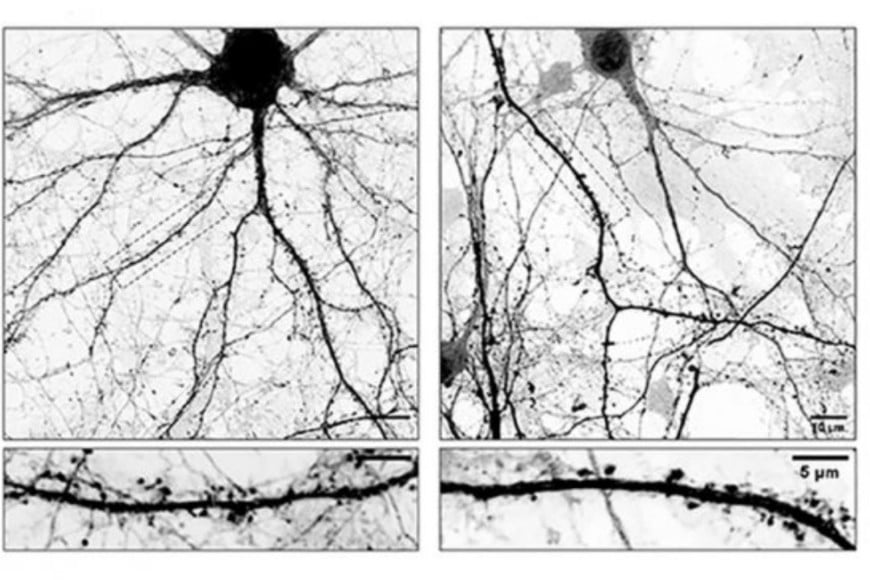

En cultivos de neuronas de ratón, la presencia de estos microtúbulos alterados se asoció a una disminución significativa de la densidad de espinas dendríticas, especialmente de las espinas maduras, consideradas las más estables y funcionales. Además, se registró una reducción en el número de sinapsis excitatorias, lo que implica una pérdida de conexiones neuronales activas.

Además, el estudio mostró que los microtúbulos modificados presentan una dinámica alterada: se desarman con mayor frecuencia y tienen menor capacidad de ingresar a las espinas dendríticas. Las espinas que no reciben esta invasión de microtúbulos resultaron mucho más vulnerables a ser eliminadas, lo que explica la reducción progresiva de conexiones sinápticas.